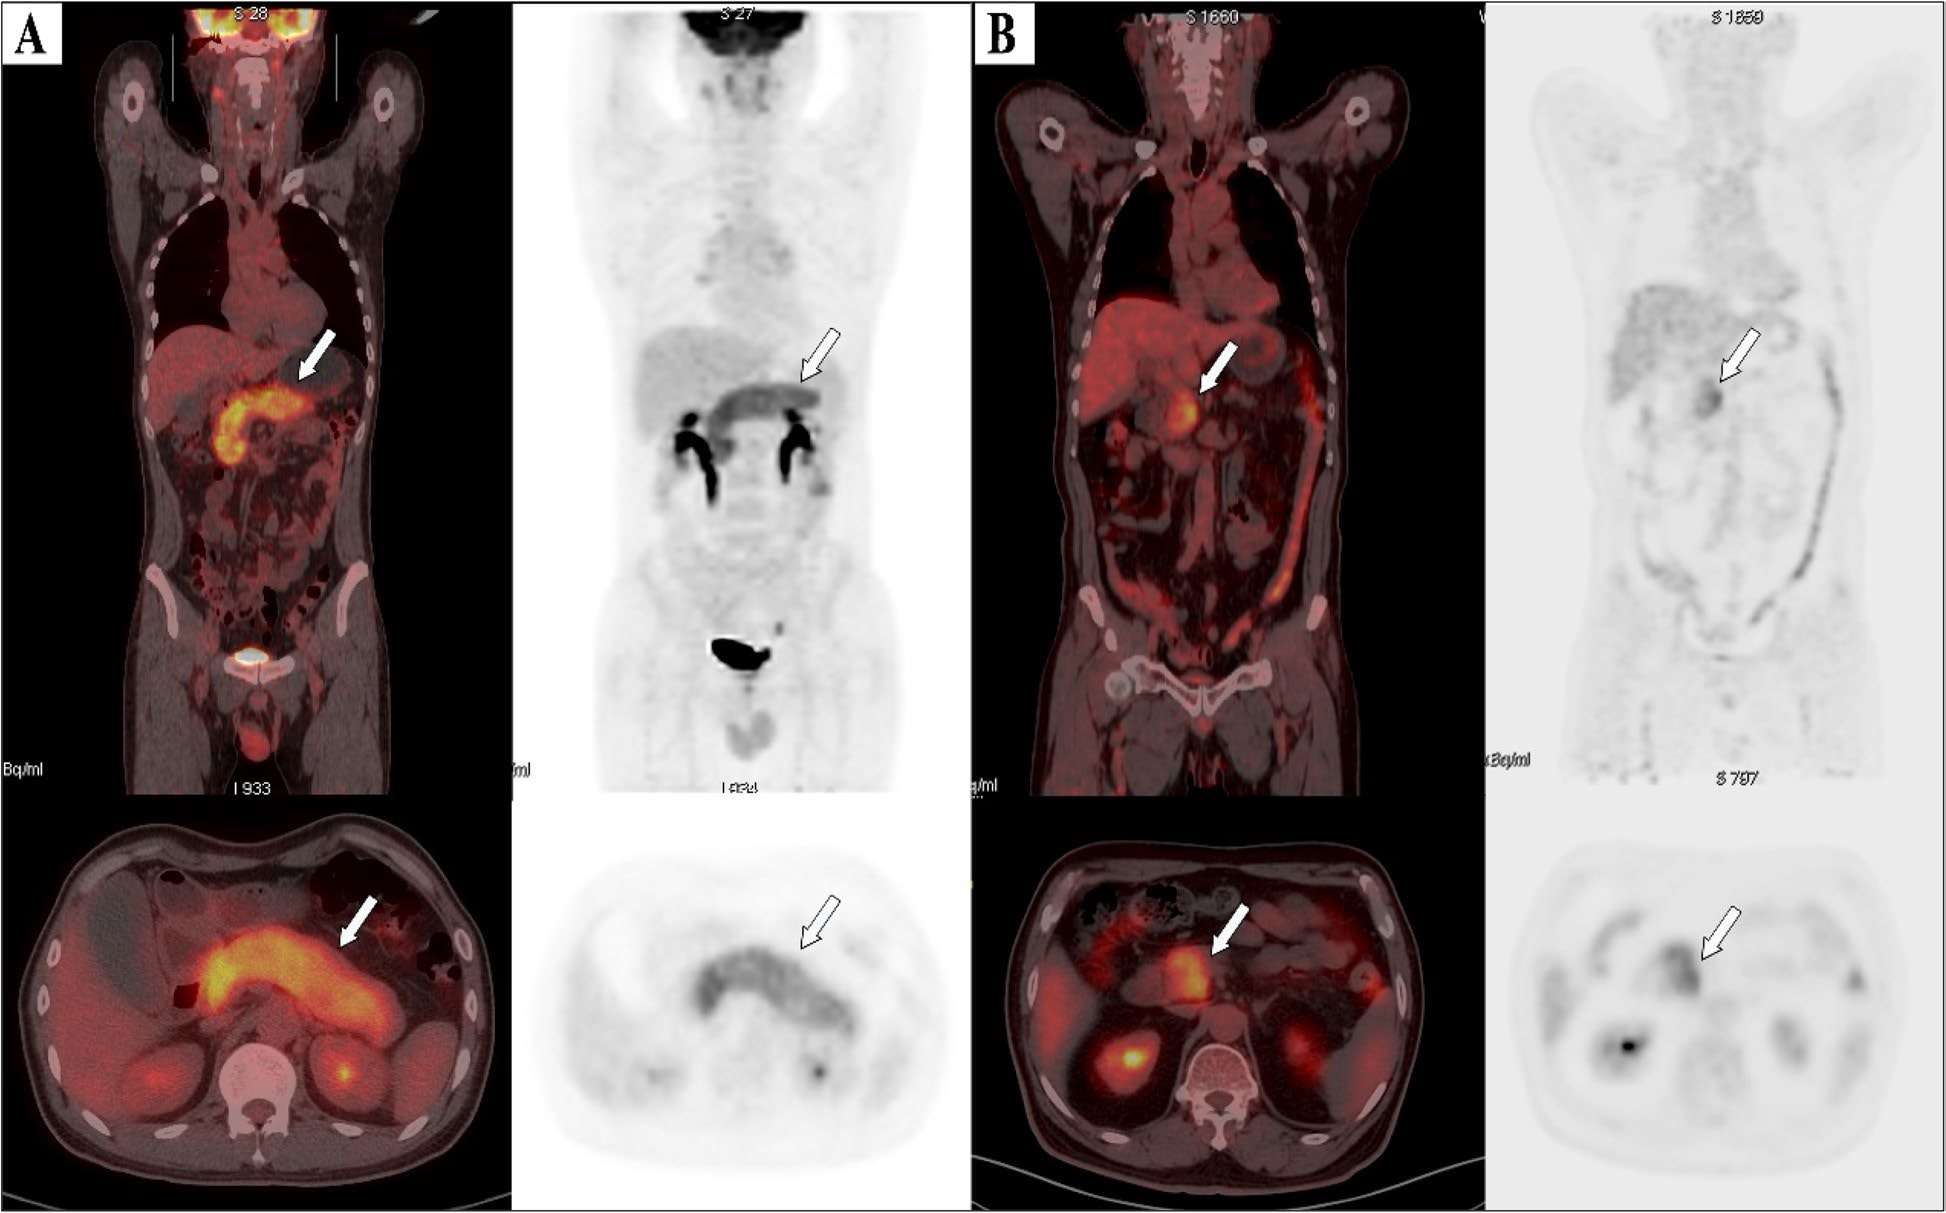

An image from Mushtaq's presentation showing a comparison between PET radiotracers in a patient with ILC. Image courtesy of Aliza Mushtaq, MD, Emory University.

In this study, Mushtaq and colleagues enrolled 20 women with new or suspected recurrent ILC from a previous trial at Emory University. Patients had undergone PET/CT scans after IV administration of F-18 fluciclovine and Ga-68 PSMA on separate days. For comparison, conventional imaging included CT or bone scans in 13 patients and F-18 FDG-PET in seven patients.

Three experts assessed radiotracer uptake per patient as well as in three regions per patient: ipsilateral axillary lymph nodes (LN), extra-axillary LNs (ipsilateral supraclavicular, internal mammary), and distant lesions (metastases).

Conventional imaging detected metastasis in five patients and in seven out of 60 regions of interest (two axillary, two extra-axillary, and three distant); Ga-68 PSMA-PET/CT detected metastasis in seven patients and in seven of 60 regions (four axillary and three distant); and F-18 fluciclovine detected metastasis in nine patients and in 13 of 60 regions (five axillary, three extra-axillary, and five distant).